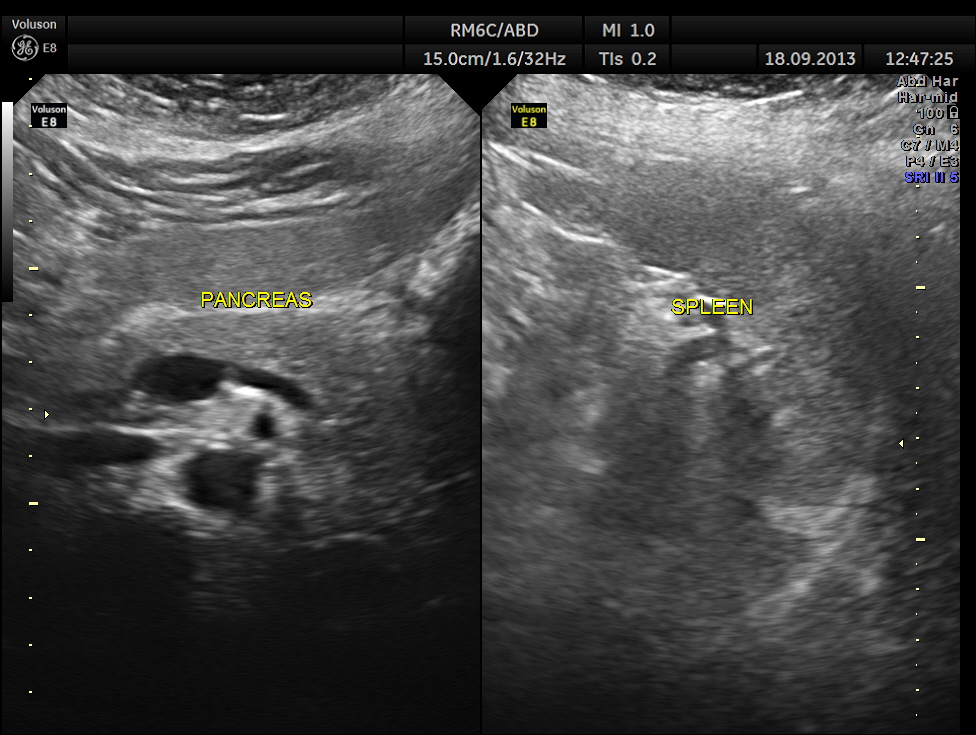

Ultrasound revealed normal liver, gall bladder, pancreas, spleen ,post menopausal shrunk uterus and normal right kidney.

The left kidney showed a calculus.